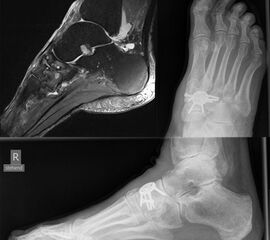

Bei zusätzlichen Sehnenpathologien kann eine Kernspintomografie hilfreich sein. Die Durchblutung sollte ebenfalls geprüft und dokumentiert werden, ferner ein neurologischer Status erhoben werden.

Die isolierte Arthrose der Bona Jäger Gelenkreihe (navikulocuneiforme Gelenk) ist selten und oft posttraumatisch. Meistens geht die navikulocuneiforme Arthrose mit einem schmerzhaften Pes planovalgus einher 2425. Letztlich werden die betroffenen Gelenkflächen angefrischt und mittels verschiedener Implantat-Möglichkeiten (s.o.) fusioniert. Bei gleichzeitiger Plattfußfehlstellung sollte diese ebenfalls adressiert werden 26 (Abb. 4). Ziel ist die Arthrodese in anatomischer Stellung der Gelenke.

Die Operation erfolgt meist über einen medialen Zugang. Nach Entknorpeln der  Gelenkflächen und Anfrischen des subchondralen Knochens kann die Arthrodese mit Schrauben oder Plattensystem erfolgen (Abb. 5). Bei Fehlstellungen muss diese vor der Osteosynthese korrigiert und das Talonavikulargelenk reponiert werden. Pseuarthrosen werden hier zwischen 8-25% angegeben 3223.